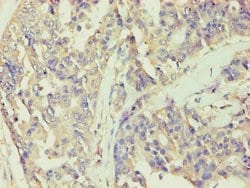

BCKDK Polyclonal Antibody for Western Blot, IHC (P), ELISA

| ELISA, Immunohistochemistry (Paraffin), Western Blot | |